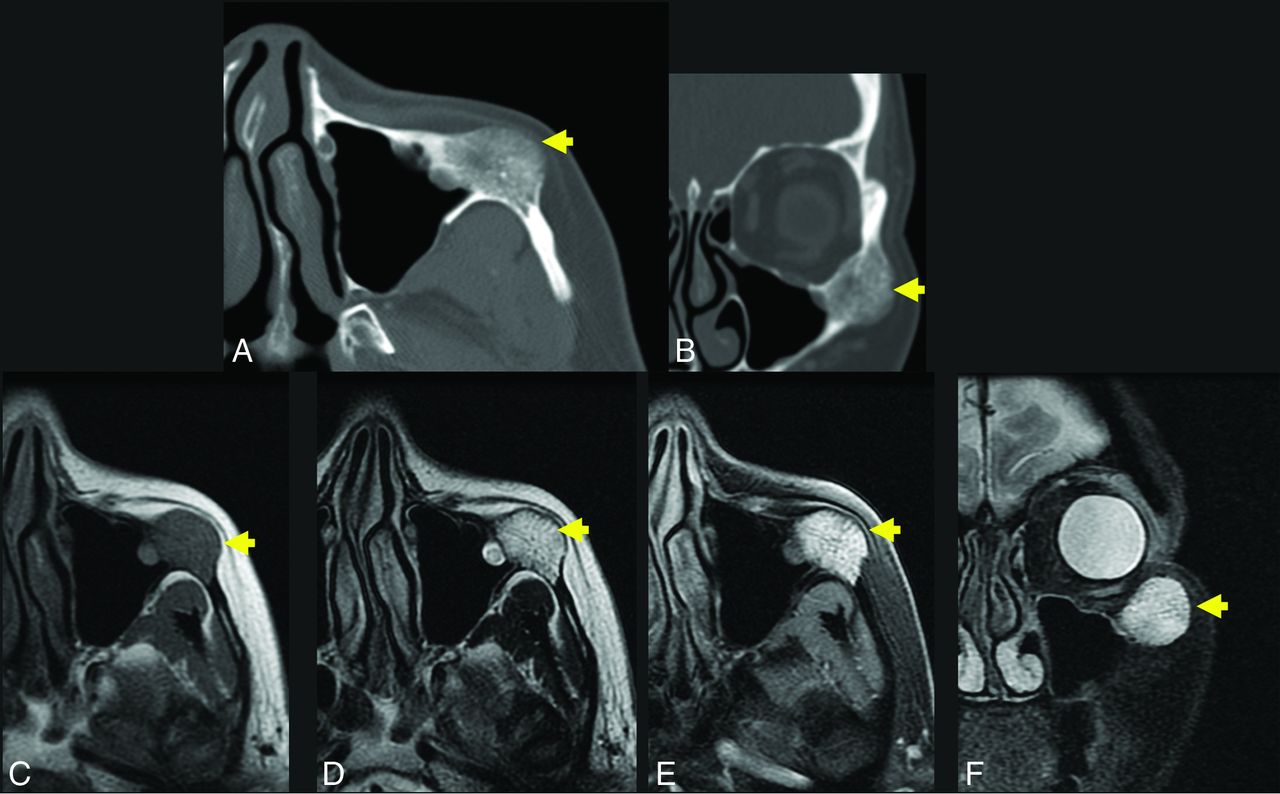

A 56-year-old woman with a palpable facial mass. The yellow arrow indicates a lesion in A–F. Axial (A) and coronal (B) thin-section CT in bone windows demonstrates an expansile, low-density lesion with internal coarsened trabeculae. The characteristic internal honeycomb pattern is typical of an IOVM. Axial T1 C– (C) and axial T1 C+ FS (D) sequences demonstrate a T1-intermediate, avidly enhancing lesion that extends beyond the cortical margin; the cortex is thinned but identifiable. Axial T2 FS (E) and coronal T2 FS (F) sequences demonstrate that the lesion is markedly T2 hyperintense. The diagnosis of IOVM was made on the basis of the characteristic imaging appearance, and the lesion remained stable on surveillance imaging for 3 years. C+ indicates with contrast; C–, without contrast.

Facial Skeleton

As expected, primary IOVMs of the facial bones are more likely than calvarial lesions to present clinically as a recognizable deformity and firm, palpable masses. The maxilla is most frequently involved, with classic locations for IOVM at the malar eminence, orbital rim, and zygomaticomaxillary junction (Figs 3 and 4). Less common sites include the nasal bones and mandible.33 On occasion, the facial bones may be secondarily involved with more complex and transspatial venous malformations of the facial soft tissues. Dentition may be altered as result of a maxillary or mandibular IOVM, though jaw deformity is more commonly encountered with arteriovenous malformations.34 Surgical treatment is often pursued to correct the cosmetic deformity and/or to restore function. Imaging is necessary not only for lesion characterization and anatomic mapping before surgery but also for providing image data for navigational surgical planning. In the setting of large IOVMs, preoperative lesion embolization may be offered.24

Differential diagnostic considerations for facial IOVMs are as previously described for calvarial IOVMs and include fibrous dysplasia, primary bone neoplasm, metastasis, and myeloma. Mandibular or maxillary osteosarcoma may result in a sunburst periosteal reaction, though this is typically limited to the periphery of the lesion.35 Of course, the rapid growth of osteosarcoma represents a substantially different clinical course than IOVM.